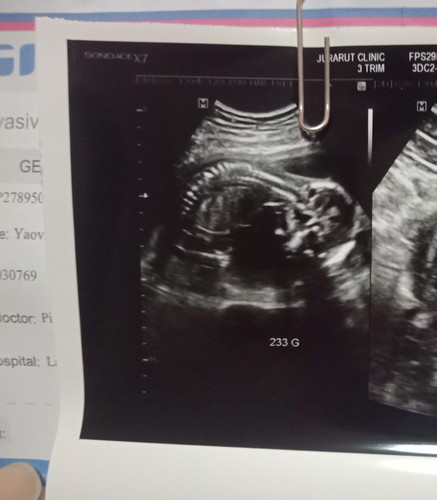

ท้อง 18 วีค ลูกนอนขวางอันตรายมั้ยคะ

ท้องแรกค่ะ ตอนซาวตื่นเต้นมัวแค่ฟังหมออธิบายเรื่องมดลูก และน้ำคร่ำ จนลืมถามว่าเด็กนอนขวางแบบนี้อันตรายมั้ย แม่ๆคนไหนเป็นแบบนี้บ้างคะ